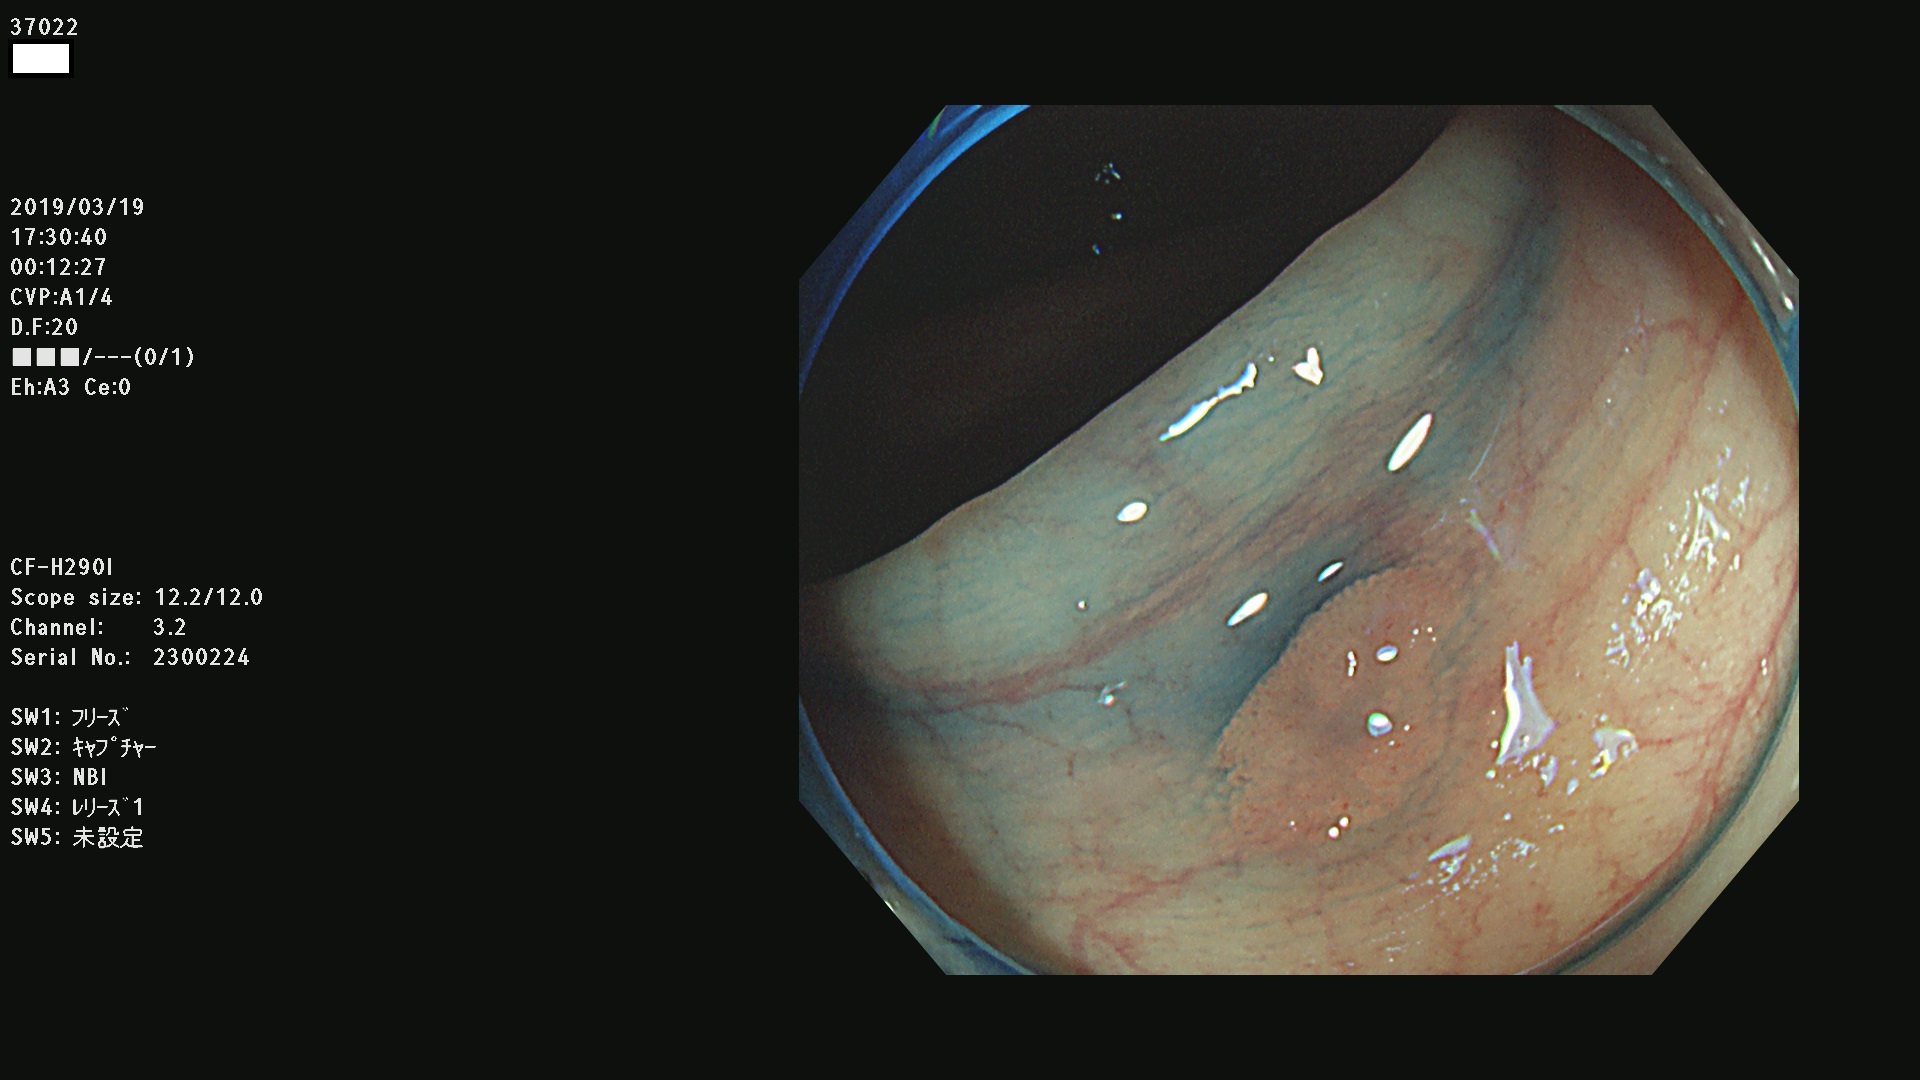

37000 37002 37004 37005 37006(SSAPのみ) 37007 37009 37013 37014 37015 37017(SSAPのみ) 37019 37020 37021 37022 37025 37026 37027 37028 37029 37031 37032 37033 37034 37035 37036 37037 37038 37041 37042 37043 37044 37045 37047 37051 37052 37053(SSAPのみ) 37055 37056 37058 37060 37061 37062 37063 37067 37072 37073 37074 37076 37077 37078 37079 37080 37081 37083 37084 37085(SSAPのみ) 37086 37087 37088 37089 37092 37093 37094 37095 37097 37098 3709

発見困難で危険性の高い平坦型病変(上記100名より抽出)